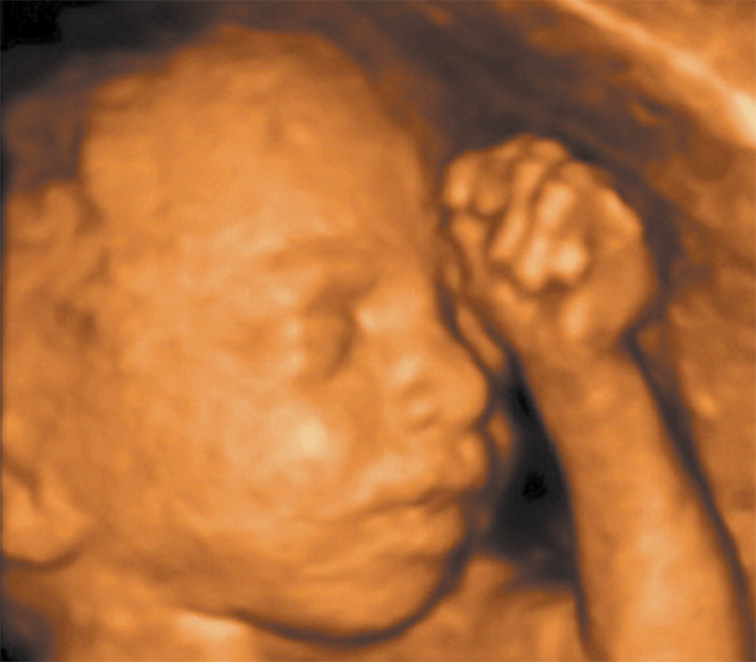

Цель 3D-ультразвукового исследования состоит в создании объемного изображения в отличие от двухмерного метода, создающего плоскостные сечения [6, 11]. Объемная картина получается при сканировании смежных сечений — это объем пространства пирамидальной формы (рис. 3, 4).

Рис. 4. Плод, 32 недели, 3D-ультразвуковое исследование / Fig. 4. Fetus, 32 weeks, 3D

На полученных сонограммах у 15 беременных визуализировались все 20 зубных зачатков. Лицо плода помещалось на экран таким образом, чтобы можно было вывести профиль, а сдвиг и вращение изображения давали возможность осмотра верхней и нижней челюсти (рис. 8, 9). У трех беременных визуализация была затруднена. С использованием плоскостей сканирования, оптимизированных для исследования конкретного органа, осуществлялась визуализация нижней челюсти целиком, включая сочленение с верхней челюстью.

Рис. 8. Лицо плода / Fig. 8. Fetal face